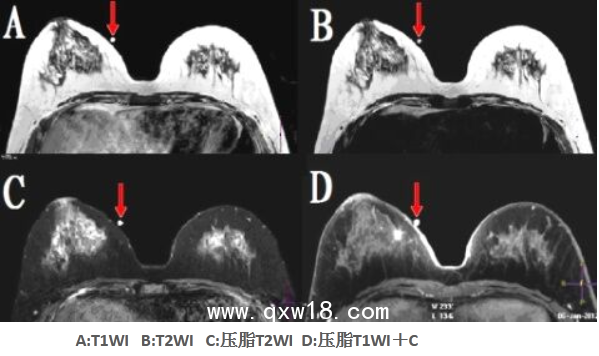

該型號(hào)定位貼尤其適用于神經(jīng)系統(tǒng)定向穿刺活檢、機(jī)器人導(dǎo)航手術(shù)等,比國(guó)外同類產(chǎn)品優(yōu)點(diǎn)突出:①球和座可組可分;配準(zhǔn)注冊(cè)孔為陽性標(biāo)記。②座受壓不變形。③在CT、T1WI、T2WI、FLAIR(壓水像)、STIR(壓脂像)等多個(gè)掃描序列上均成像明顯。④經(jīng)在北京航空航天大學(xué)研制的立體定向神經(jīng)導(dǎo)航機(jī)器人上驗(yàn)證,標(biāo)記定位的精度高于國(guó)外產(chǎn)品。1ZP_Y[BB}_PPHDOAEJFUY(S